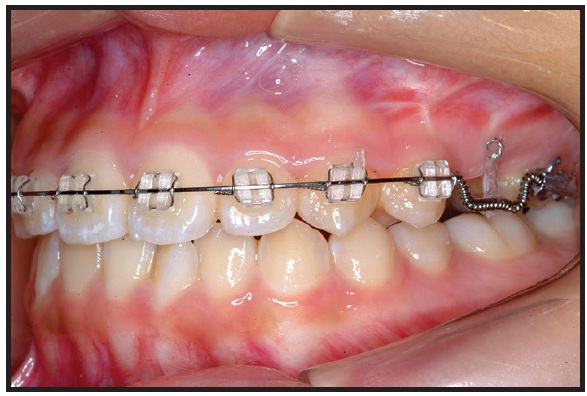

An .018" × .022" MBT-prescription Inspire ICE* clear fixed appliance was bonded in the upper arch. After three months of initial leveling on .014", .016", and .016" × .022" G4** nickel titanium archwires, an .016" × .022" stainless steel archwire was inserted. The patient was then referred for extraction of the retained tooth and exposure of the impacted premolar by an oral surgeon. A metal lingual button was bonded to the impacted tooth, and a twisted stainless steel ligature wire was tied to the attachment (Fig. 2). The ligature wire was drawn inferiorly through the sutured edges of the flap, so that the surgical site could be completely closed.

After seven days of healing, orthodontic treatment was resumed. Traction was applied to the twisted stainless steel ligature to bring about full eruption of the tooth. Since the distance between the ligature wire and the main archwire was too short to apply force, a stepdown bend was made in the archwire, and an open-coil spring was inserted between the first molar and first premolar to open and maintain adequate space for the second premolar (Fig. 3). The progress of impacted tooth movement was evaluated monthly (Fig. 4). After three months, to produce more clockwise rotation of the impacted tooth, the metal button was replaced by a minitube and an .016" × .022" TMA*** auxiliary wire was bent and attached (Fig. 5). Three months later, the wire was activated to create an additional rotational moment (Fig. 6).

Fig. 2 After three months of upper leveling and alignment, metal lingual button bonded to impacted upper left second premolar, and twisted stainless steel ligature wire tied to attachment.

Fig. 3 After one week of healing, stepdown bend made in main .016" × .022" stainless steel archwire to increase distance for eruption force application; open coil spring inserted between first molar and first premolar to open space for second premolar.